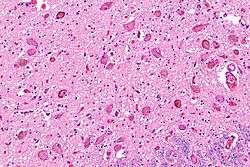

![]() Micrograph showing the locus coeruleus. HE-LFB stain. | |

Anatomy

The locus coeruleus (or "LC") is located in the posterior area of the rostral pons in the lateral floor of the fourth ventricle. It is composed of mostly medium-size neurons. Melanin granules inside the neurons of the LC contribute to its blue color. Thus, it is also known as the nucleus pigmentosus pontis, meaning "heavily pigmented nucleus of the pons." The neuromelanin is formed by the polymerization of noradrenaline and is analogous to the black dopamine-based neuromelanin in the substantia nigra.